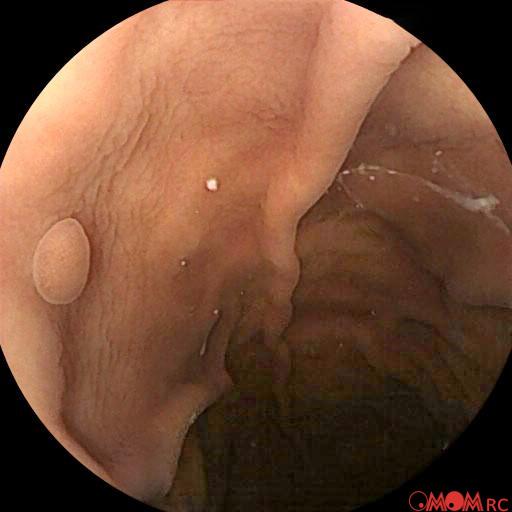

Typical Findings

Polyp Erosion Gastritis Ulcer